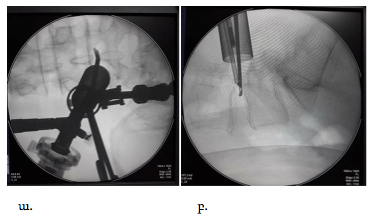

Մասնակի երկկողմանի նյարդարմատիկային համախտանիշ ունեցող հիվանդների խմբում վիրահատությունը շարունակվում էր հետևյալ կերպ՝ ոսկրակրծիչը տեղադրվում էր դուրալ պարկի վրա և կատարվում էր ոսկրային և կապանային հյուսվածքի հեռացում վենտրալ մակերեսից: Ուղղելով աշխատանքային խողովակը որոշակի մեդիալ անկյանտակհնարավոր էր դառնում աքցաններով կամ ոսկրակրծիչներով հասնել ողնաշարային խողովակի կոնտրլատերալ սահմանին և կատարել հակառակ կողմի դեկոմպրեսիա /նկար 8/

Նկ. 8 պատկերված է ողնաշարային խողովակի կոնտրլատերալ հատվածի դեկոմպրեսիան

ա. ռենտգեն հետազոտում առաջահետին պրոեկցիայում: Ձախակողմյան վիրաբուժական մուտքից տեղադրված աքցանի ծայրերը գտնվում են ողնաշարային խողովակի /կոնտրլատերալ/ աջակողմյան հատվածում, բ. նույնը կողմնային պրոեկցիայում: Աքցանի ծայրերը գտնվում են միջողային աճառի եզրին և խորասուզված չեն նրա մեջ

Այն հիվանդների խմբում, ում մոտ առկա էր երկկողմանի խիստ արտահայտված նյարդարմատիկային համախտանիշ, վիրահատությունը կատարվում էր բիպորտալ մուտքերով՝զուգահեռ երկու կողմերից կատարվում էր հեմիլամինէկտոմիա:

Կիրառվող էնդոսկոպիկ տեխնիկան թույլ էր տալիս կատարել վիրահատությունները նույնիսկ 2 կամ 3 մակարդակի ողնաշարային խողովակի նեղացման (ստենոզի) դեպքում: Վիրահատության առանձնահատկությունը կայանում էր նրանում, որ միաժամանակ կատարվում էր մեկական փոքր կտրվածք նեղացման ենթարկված ամենմակարդակներին, որից հետո միաժամանակ տեղադրվում էին երկու աշխատանքային խողովակներ և հաջորդաբար կատարվում էր նեղացման ենթարկված մասի բացազատում, ինչը ցույց է տրված նկար 9-ում:

Նկ. 9 Երկու մակարդակի ողնաշարային խողովակի նեղացման էնդոսկոպիկ վիրահատման ներվիրահատական նկար

ա. զուգահեռ տեղադրված երկու աշխատանքային խողովակներ

բ. Նույնը ռենտգեն հետազոտմամբ կողմնային պրոեկցիայում